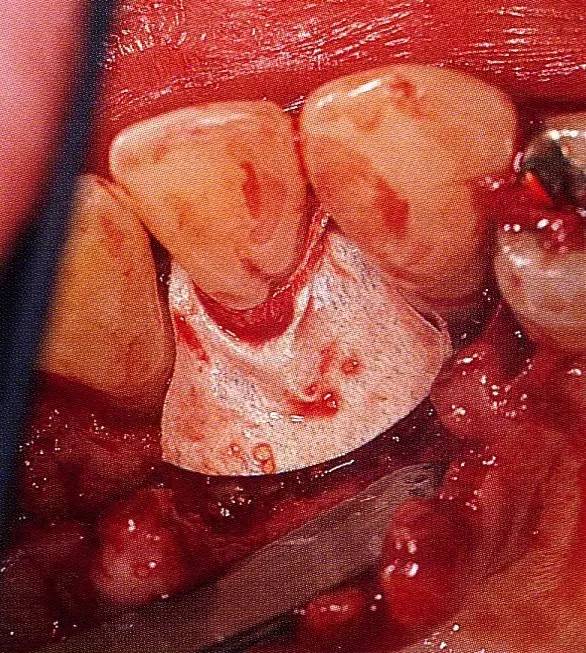

▲圖7-4  術(shù)后1年2個月再翻開看的情況。與圖7-1的骨缺損狀態(tài)相比可知形成了臨床性骨再生。

▲圖7-5  此狀態(tài)下,左下5的遠中存在牙槽骨不平整,因此進行了骨修整。同時,將骨膜留存,進行了齦瓣根尖側(cè)移動術(shù),去除了牙周袋。